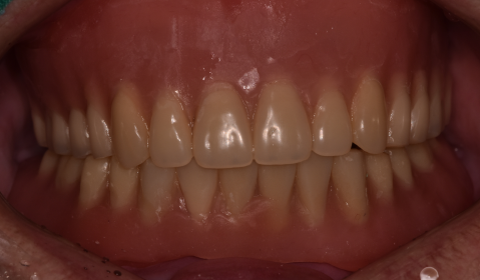

하악 부분 틀니 및 상악 전체 틀니 제작 후

따라서 아래쪽 앞니 쪽에 틀니를 잡아줄 수 있는 임플란트 두 개를 식립하여 두 개의 임플란트들을 연결하여 아래 앞니 6개를 만들어 드린 후, 어금니쪽은 부분 틀니로 보강하는 치료 방법을 선택하였습니다. 위쪽은 전체 틀니를 만들어 드렸습니다.

임플란트를 이용하여 부분적으로 치아를 만들고, 이 치아에 일정 부분의 힘을 지탱시키는 형식의 부분틀니는 전체 틀니에 비해 씹는 힘에 잘 버티고 혀나 볼의 움직임에 틀니가 탈락하지 않아 치료가 잘 마무리 되었습니다.